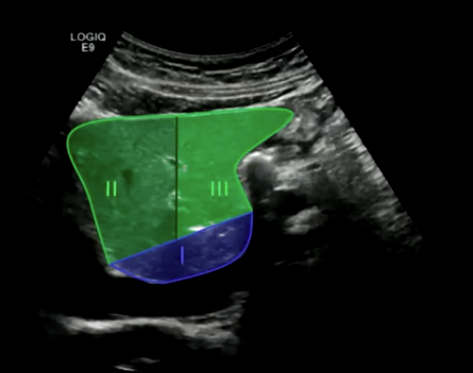

Left Hemi Liver:

Segments two, three, and four. These segments are supplied by the left hepatic artery and portal vein branch.

Thumb: Caudate lobe (segment one). The caudate lobe receives blood supply from both the right and left hepatic arteries and portal vein branches.

Falciform ligament separates segments two and three from segment four. This is a key landmark for dividing the left lobe.

Aorta: Superior segment two, inferior segment three. The aorta is a useful landmark for identifying these segments.

IVC: Segment one (caudate lobe), segment three, and segment two. The IVC is located posterior to the liver.

Gallbladder: Segment four. The gallbladder is located in the gallbladder fossa of segment four.